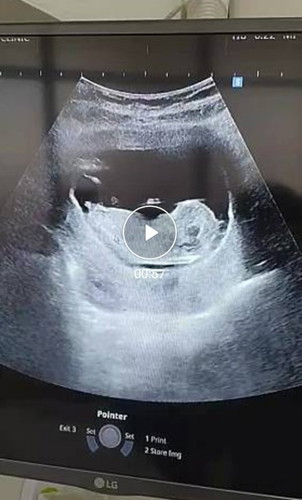

ตอนวัยรุ่นตอนปลายๆ เคยไปหาคุณหมอเพราะประจำเดือนไม่ปกติ หมอบอกเป็น PCOS จนเวลาผ่านไปตอนนี้อายุ 32 ปีแล้ว ตั้งท้องแรกกลับไปฝากครรภ์กับคุณหมอท่านเดิม คุณหมอบอกเก่งมาก ตั้งท้องได้เองธรรมชาติ เราดีใจมากเลยกลัวจะอายุมากไปกว่านี้ แม่ๆ ท่านเคยเป็น PCOS แล้วท้องได้เองกันบ้างคะ แชร์กันหน่อย